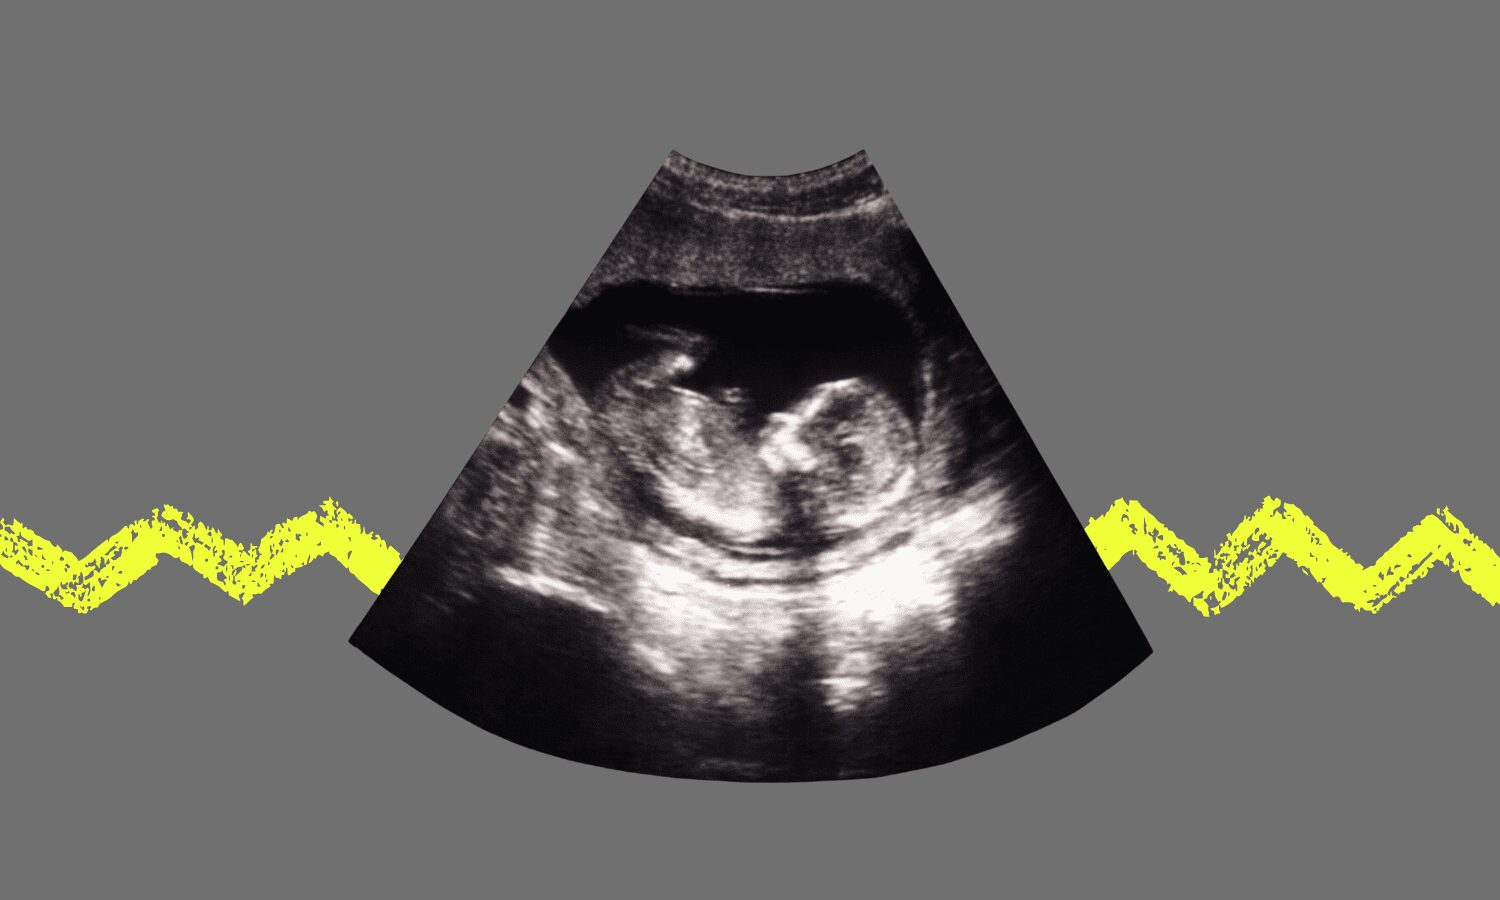

¿Puede haber algo más importante que ayudar a dar vida? Quizá en un mismo grado de importancia se sitúa el acompañamiento a esa criatura recién llegada durante sus primeras semanas o meses de vida. Pero el alumbramiento, el acto de desunir la simbiosis con el cuerpo materno, es la acción primigenia de la andadura existencial. Y las que se encargan de ello son las matronas, o las parteras, esas mujeres que desde hace siglos dan la bienvenida al mundo a cada bebé.

Y es que el momento del alumbramiento en nuestra especie es muy diferente al de los homínidos más parecidos, los primates. Sus partos son rápidos, en apenas unos segundos los esfuerzos de la madre desaparecen y la criatura ha nacido. En su estudio Nacimiento, obstetricia y evolución humana, las antropólogas Werida Trevathan y Karen Rorenberg explican: «El ser humano desarrolla una conducta única en relación al parto. Al contrario que el resto de los primates, que eligen la soledad para dar a luz, las madres humanas buscan activamente ayuda en el parto. Así surgió un modelo de parto en el que una matrona es fundamental». Y es que el gran tamaño de nuestro cerebro y el bipedismo precisaron de la búsqueda de otras técnicas a la hora del parto.